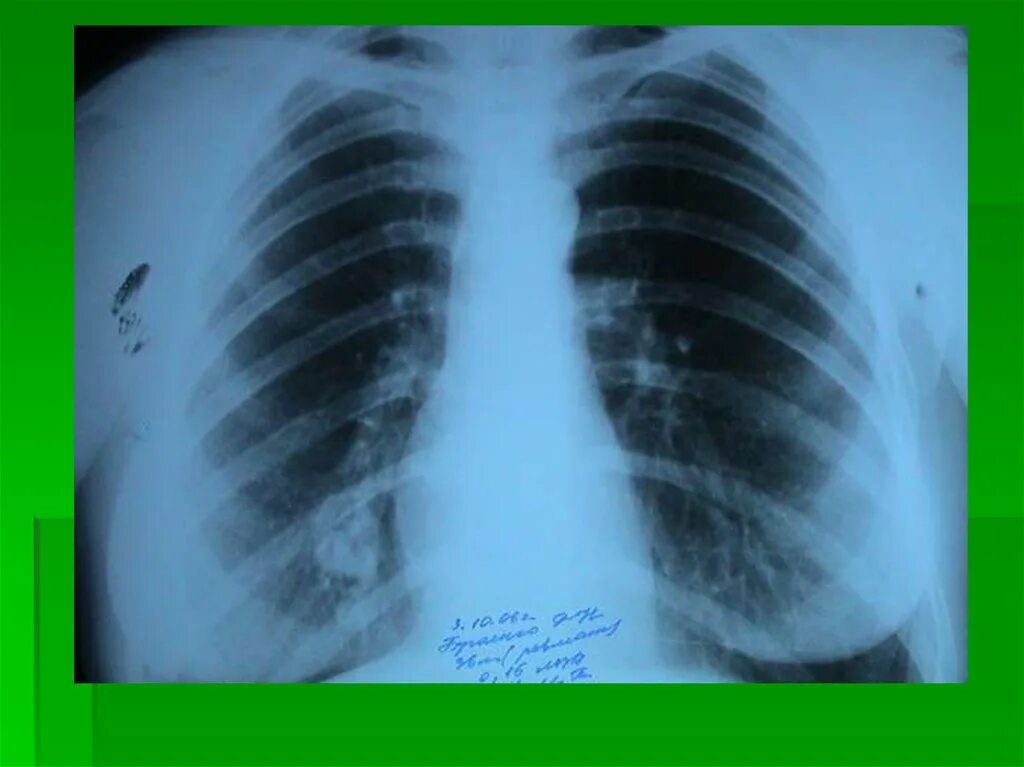

Бронхоаденит это